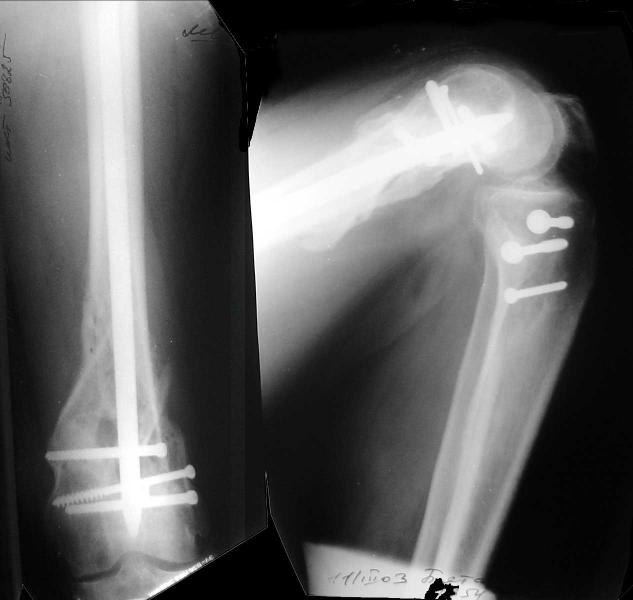

Re: Open supracondylar femur fx

Alexander Chelnokov 31 Октябрь 2004, 20:44

And why LISS is superior here than nail?

Look what we would have done.